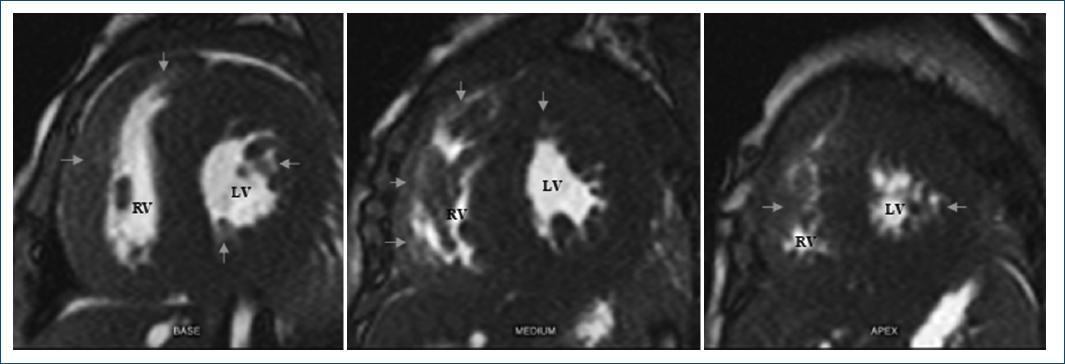

The echocardiogram showed concentric biventricular hypertrophic without and decreased left ventricular function. Late intramyocardial low-septal, middle, and apex enhancement were detected in the magnetic resonance (Figs. 1 and 2). The Genetic screening reported Gene GAA variant c.1987del (p.Gln663serfs*33) compatible with PD. Fifteen days after admission, he died of ventricular fibrillation.

Figure 2 Magnetic resonance images in short-axis plane, present cardiomyopathy with late low, middle, and apex intramyocardial enhancement (arrows). RV: right ventricle; LV: left ventricle.